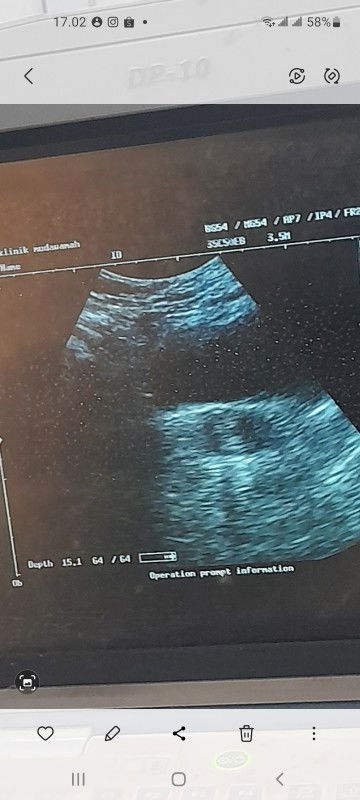

Ada yang bisa jelasin ke saya tentang masalah ini ? Jadi saya sudah telat haid selama 1bulan. Awal" telat saya test hasilnya memang negative. Tapi badan ngerasa kaya ga enak. Dan awalnya saya kira saya masuk angin karna sering mual sama sendawa. Tapi tetep aja masih mual Tapi gak intens. Lalu karna ngerasa badan saya tetap ga enak akhirnya saya test lagi dan hasilnya tetap saja negative. Tapi suami saya menyarankan untuk cek ke dokter takutnya ada penyakit. Akhirnya saya periksa. Dan waktu periksa itu si dokter bilang ternyata saya sudah hamil 5week. Saya masih belum percaya karna testpack menunjukan hasil negative terus. (Dan foto USG ada di slide pertama ) dan karna saya masih ada anak kecil juga akhirnya saya di beri obat penguat. Beberapa hari terlewat badan emang kaya nunjukin lagi hamil. Masih sering mual juga Dan perut terkadang keram dan sedikit buncit. Tapi saya masih belum percaya sama hasil usg pertama akhirnya saya periksa lagi. Dan di dokter yang berbeda. Ternyata hasil usg menunjukan rahim saya masih Normal dan tidak hamil. Jadi saya semakin bingung. Tapi memang testpack masih menunjukan hasil negative. Kira" ada yang sepengalaman ga bund? Apa berati saya tidak hamil dan Dr pertama salah prediksi? #SeriusTanya #bantujawab #ingintahu

bener" di buat OVT. Dari awal telat sampe sekrang testpack menunjukan hasil negative. Tapi waktu itu udah pernh USG dan Dr.nya bilang kalo udah hamil 5week. Ya allah jadi bingung aku beneran hamil atau tidak. Dan gada mulmun sama sekali. Cuma awal" doang habis itu lancar Jaya sentosa. Kek gak hamil. Kira" ada yang sepengalaman gasih. Tolong beri aku pencerahan. Btw yang aku rasain sekarang cuma sering Kentut dan sendawa aja. Tp perut emang agak buncit sih. #bantujawab #SeriusTanya #ingintahu